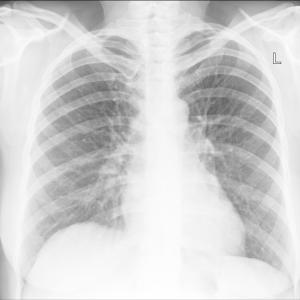

Hypocalcaemia tied to mid-, long-term death in acute pulmonary thromboembolism

Low serum calcium in patients with acute pulmonary thromboembolism (PTE) independently predicts 30-day and long-term mortality, suggests a China study that used a new prognosis assessment model.

30 Aug 2022